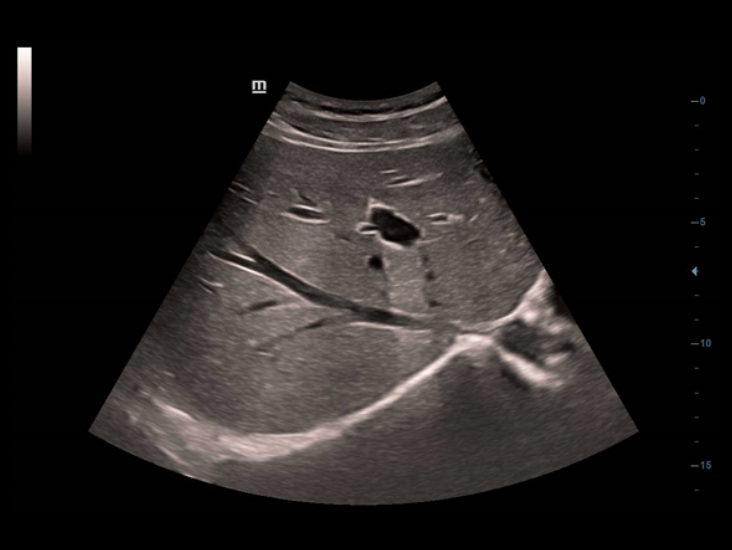

TecnologĂas de imagen clĂĄsicas: aumenta la calidad del diagnĂłstico

Mediante la aplicaciĂłn de tecnologĂas de imagen clĂĄsicas, que se migran desde los sistemas de ultrasonido establecidos, DC-40 con Full HD le proporciona una calidad de la imagen mĂĄs detallada y nĂtida.

- iClear (TecnologĂa de imagen con reducciĂłn de moteado)

- PSH (ImĂĄgenes por armĂłnicos con desplazamiento de fase)

- iBeam: tecnologĂa de formaciĂłn de imĂĄgenes espaciales compuestas